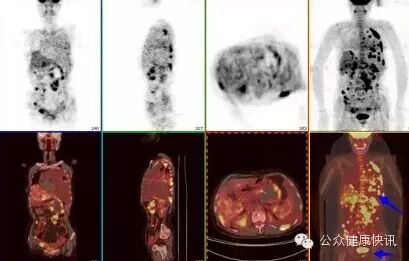

PET-CT

正电子发射计算机断层显像

建议检查:全身及转移性实体肿瘤。

PET检查(发现代谢异常细胞)+CT检查(发现形态异常组织),先注射放射性药物,再行CT扫描。

特长:癌症病人的诊断、鉴别诊断、疗效评估、临床分期。

肝癌的PET-CT检查结果